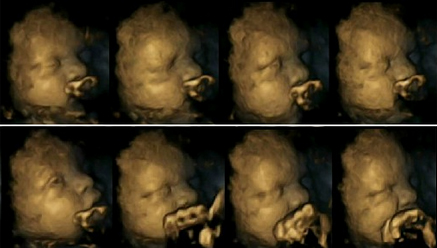

Pamjet e nje foshnje ne barkun e nje nene joduhanpirese

Në studim u vu re se foshnjet e nënave joduhanpirëse ishin më të qetë në bark dhe lëviznin më pak në krahasim me foshnjet e palindura të nënave duhanpirëse, që vinin duart më shpesh në gojën dhe fytyrën e tyre.